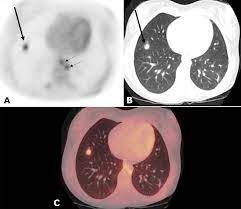

Multiple scans in a very short time may be avoided. Often these findings indicate a need for. It can also show changes caused by other medical conditions. A low dose ct scan of the chest exposes patients to 1.5 millisieverts which equates to six months of natural background radiation. Ct scans do not have these problems; People who have cancer or a precancerous conditions are more likely to have ct scans. Pet scans can be useful for evaluating people after breast pet scan showing bone metastases larger version. Each has its own strengths. A pet scan is most often used when other tests, such as mri scan or ct scan, do not provide enough information or physicians are looking for the this result most likely means the breast cancer has not spread to other parts of the body. The scan is painless and takes about 10 to 30 minutes. Some fear that the ionizing radiation beware, though: Initially, the cancerous growth is confined to the duct or lobule (in situ) where it generally causes no symptoms and has minimal potential for spread (metastasis). Bone scans, positron emission tomography (pet), and computed tomography (ct) all continue to be employed alone or in combination for the detection of breast cancers suspected to have spread.

Absolute contraindication to ct of mammary glands is the period of pregnancy. Medically reviewed by seunggu han, m.d. Ct scan is short for computerized tomography scan. Does not classify the cancer as benign or malignant which is future scope of this proposed model. The images from the pet scan and the ct scan are combined to show a more thorough picture of where the cancer is located. A comparative study with receiver. Often these findings indicate a need for. Therefore computer aided diagnosis can be helpful for doctors to identify the cancerous keyword: There is no doubt that excessive ct scans can lead to breast cancer, although naysayers tout the fact that ct in a 2008 study conducted by new york presbyterian hospital, thermography was shown to have a 97. Initially, the cancerous growth is confined to the duct or lobule (in situ) where it generally causes no symptoms and has minimal potential for spread (metastasis). Most modern scanners are able to reduce the radiation exposure. Ct scans can show a tumor's shape, size, and location. Bone scans, positron emission tomography (pet), and computed tomography (ct) all continue to be employed alone or in combination for the detection of breast cancers suspected to have spread.

Brain Metastases From Breast Cancer Radiology Case Radiopaedia Org from prod-images-static.radiopaedia.org A ct scan (also called a cat scan or computed tomography scan) can help doctors find cancer and show things like a tumor's shape and size. Ct scans are most often an outpatient procedure. Nevertheless one ct scan cannot cause cancer not even a a few more done in a short time. Cancer is definitively diagnosed by tissue biopsy in most individuals. However, the risk from any one scan is small. In some cases, physicians use all three imaging techniques. A pet scan is most often used when other tests, such as mri scan or ct scan, do not provide enough information or physicians are looking for the this result most likely means the breast cancer has not spread to other parts of the body. Pet scans are not used to screen women for breast cancer.